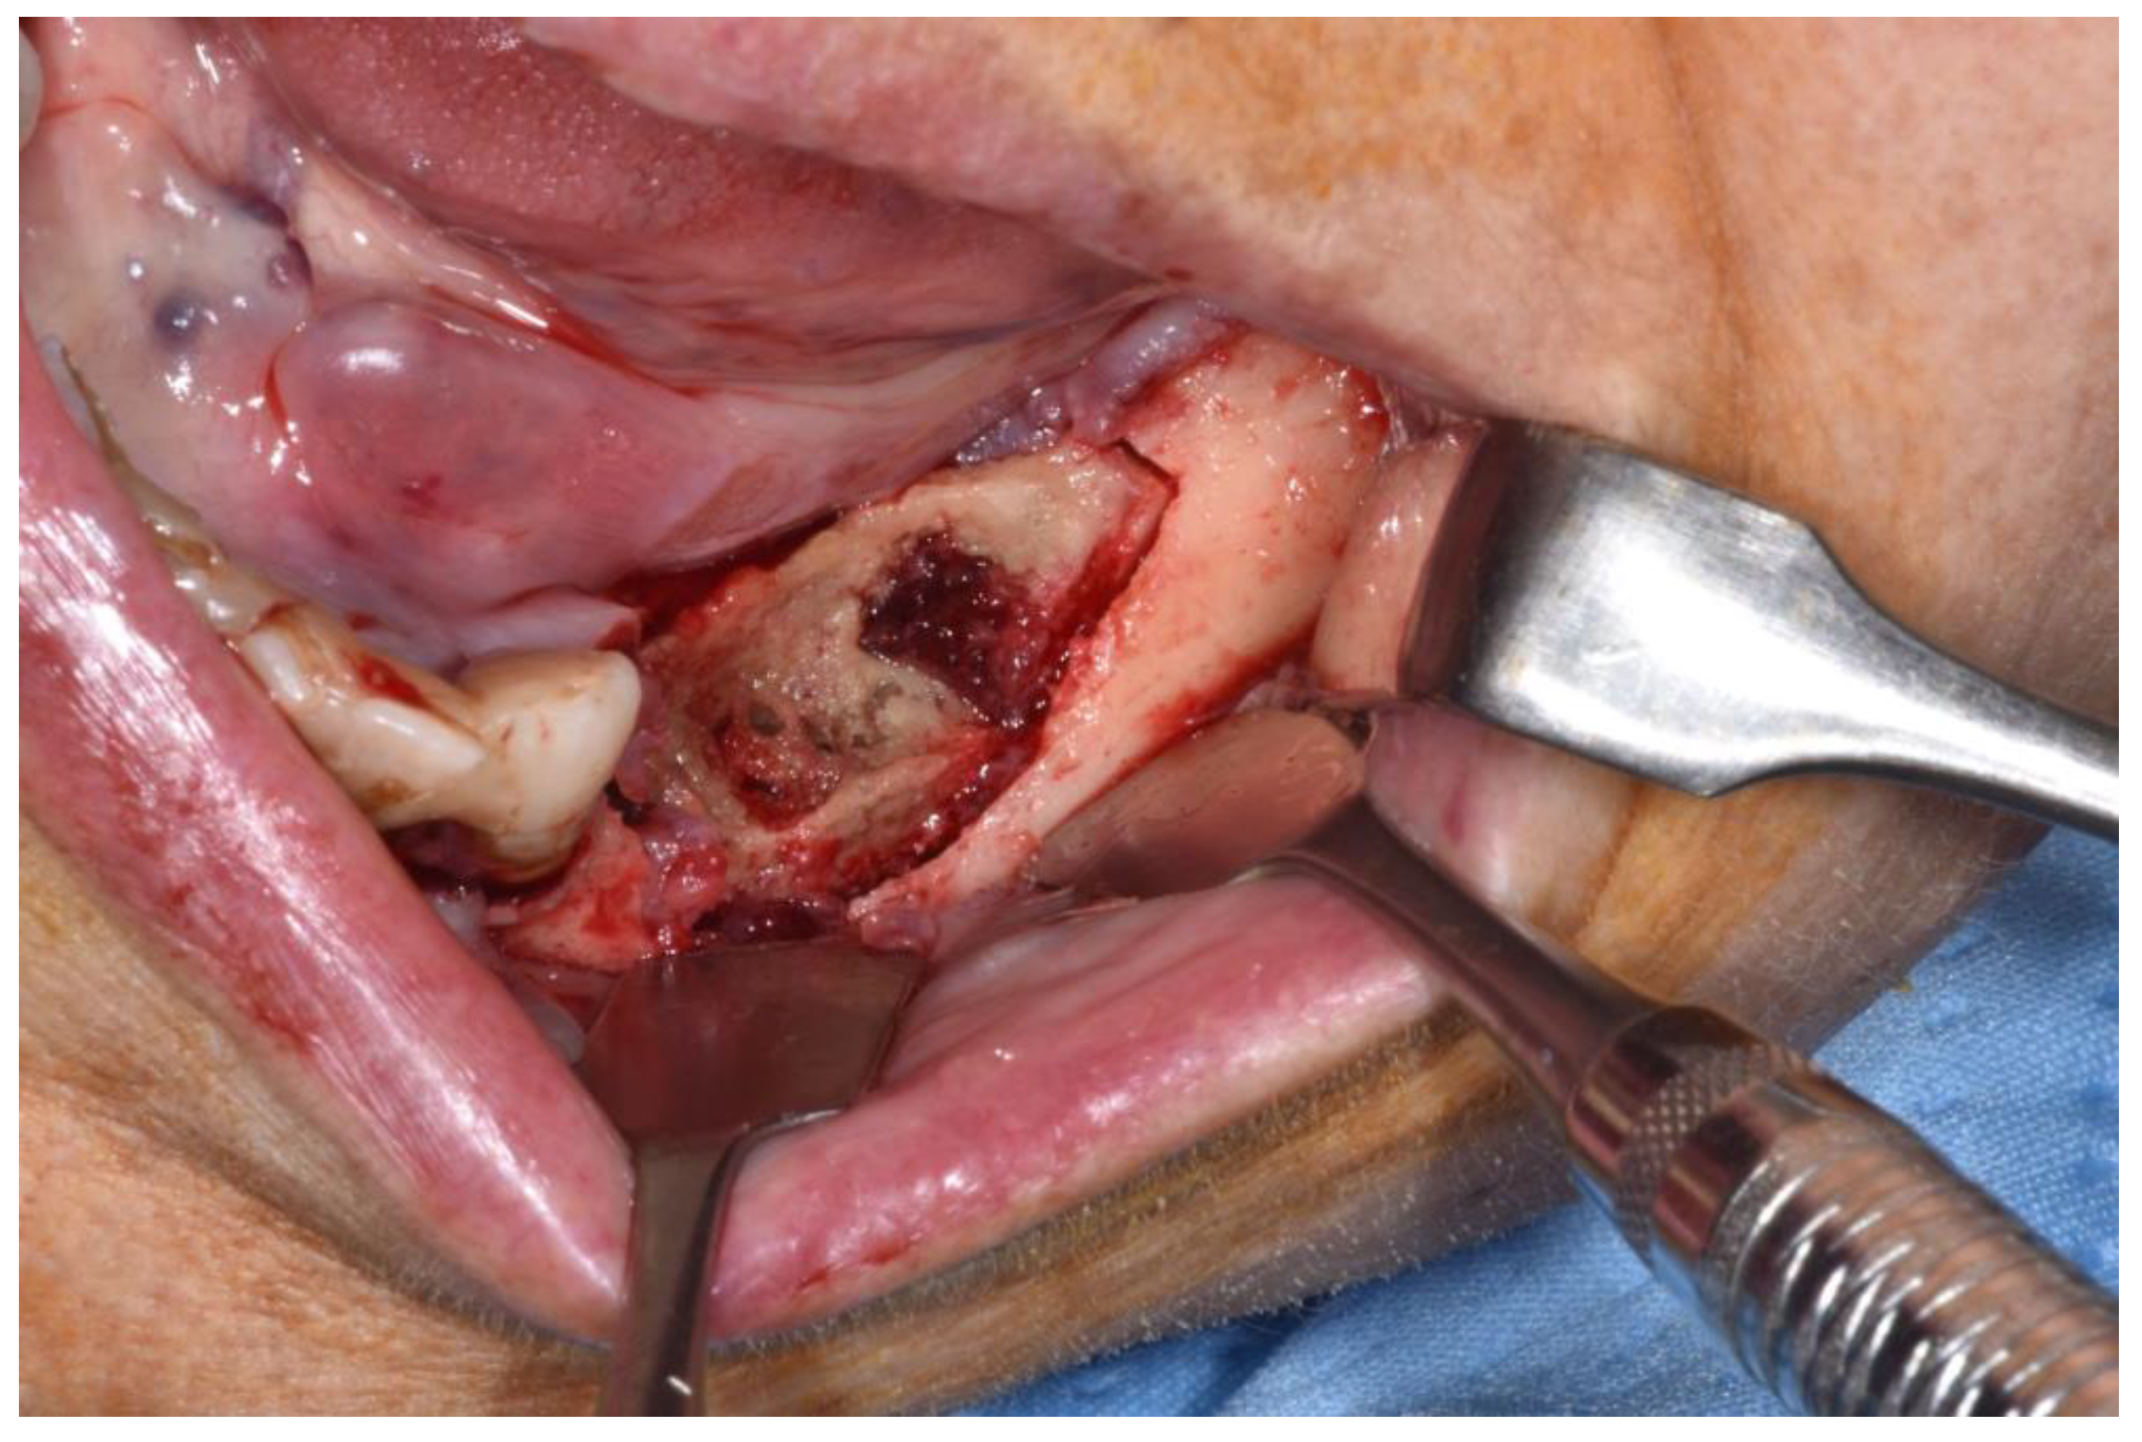

Figure 3.

Clinical appearance when elevating mucoperiosteal flap.

Patients are referred to the Osteonecrosis of the Jaw Treatment Center, School of Dentistry, University of Messina mostly by their oncologist. On arriving at the center, patients are diagnosed with MRONJ based on the clinical and radiological findings in order to distinguish focal and diffused forms. Routine procedures at first examination include oral swab and pharmacological treatment prescription with systemic antibiotics. Initial treatment is amoxicillin plus clavulanic acid in combination with metronidazole at 250 mg; subsequently, patients are switched to targeted antibiotic therapy on the basis of the antibiogram result. Eight to ten weeks after the initiation of pharmacological treatment, unchanged and progressive forms urdergo surgical treatment [34]. The systematic application of this work flow ensures homogeneity in the patient sample in terms of antibiotic therapy (empiric vs. targeted therapy) and time to intervention (defined as time from MRONJ diagnosis to surgical procedure). The surgical approaches were defined according to literature [9,10,17,23,35,36] as previously described by our study group [25,26]. The surgery was performed in loco-regional anesthesia with intra-oral approach and consisted in the resection of the necrotic bone until reaching bleeding vital bone. Access to the osteonecrotic lesion was provided by a mucoperiosteal flap with total thickness sufficiently large to include the margins of the necrotic bone. The affected bone can be removed using ultrasonic bone surgery device. After removing the necrotic segment, if a sufficient quantity of soft tissue to obtain closure by first intention is present, the vestibular and the lingual mucoperiostal flaps were directly sutured on the defect without any release incision; otherwise, closure could be obtained using mucosal advancement flaps to allow for a tension-free suture. Figure 1, Figure 2, Figure 3, Figure 4, Figure 5 and Figure 6 show pre-surgical assessment and specimen harvesting during surgical procedure (Figure 1, Figure 2, Figure 3, Figure 4, Figure 5 and Figure 6).